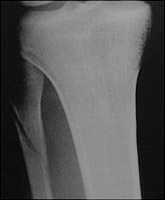

- Click on the image for a larger versionBAP radiograph of the upper tibia and fibula. This shows a fracture of the proximal fibula. This is a Maisonneuve fracture.